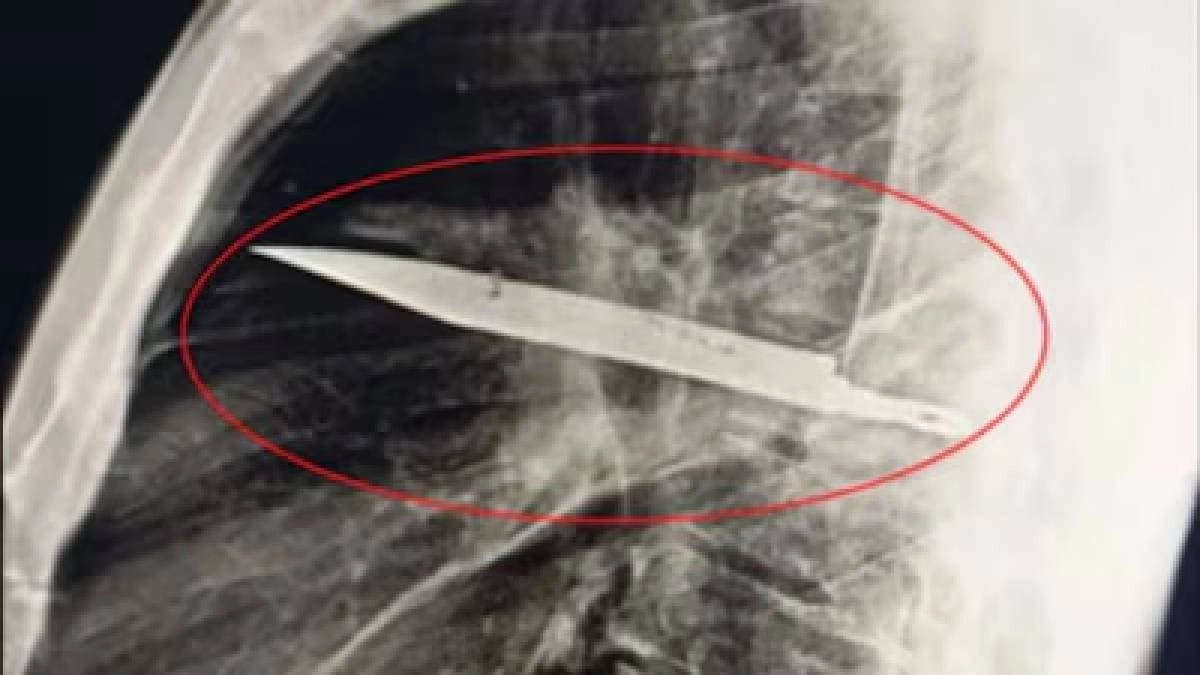

চিকিৎসকরা তাঁর বর্তমান সংক্রমণের কারণ অনুসন্ধান করতে গিয়ে এক্স-রে করেন। এক্স-রে রিপোর্টে দেখা যায় তাঁর বুকের মাঝামাঝি অংশে একটি ধাতব বস্তু রয়েছে, যার চারপাশে ধোঁয়াটে ছায়ার মতো চিত্র দেখা যায়। এই চিত্র থেকে বোঝা যায় সেখানে দীর্ঘদিনের জমে থাকা রক্ত বা ট্রমার পরবর্তী টিস্যু পরিবর্তন (ফাইব্রোসিস) হয়েছে। চিকিৎসকরা জানান, এটি সম্ভবত পুরনো ছুরির আঘাতের ফলে হয়েছে।

আজকাল ওয়েবডেস্ক: তানজানিয়ার মুহিমবিলি ন্যাশনাল হাসপাতালে এক বিস্ময়কর ঘটনা ঘটেছে। সূত্রে জানা গিয়েছে চিকিৎসা করাকালীন চিকিৎসকরা এক ব্যক্তির বুকের ভেতরে আটকে থাকা একটি বড় ছুরির ফলা আবিষ্কার করেছেন, যা প্রায় আট বছর ধরে অজানাই রয়ে গিয়েছিল। ব্যক্তির বয়স ৪৪ বছর। ওই ব্যক্তি হাসপাতালে আসেন ডান বুকে ব্যথা এবং স্তনবৃন্ত (নিপল) থেকে পুঁজ বের হওয়ার অভিযোগ নিয়ে। এরপর তার এক্স-রে করতে চিকিৎসকদের চোখ কপালে। দেখা গিয়েছে, ব্যক্তির বুকের মধ্যে একটি ধাতব বস্তু আটকে আছে, যা অনেকটা ছুরির ফলার মত দেখতে।